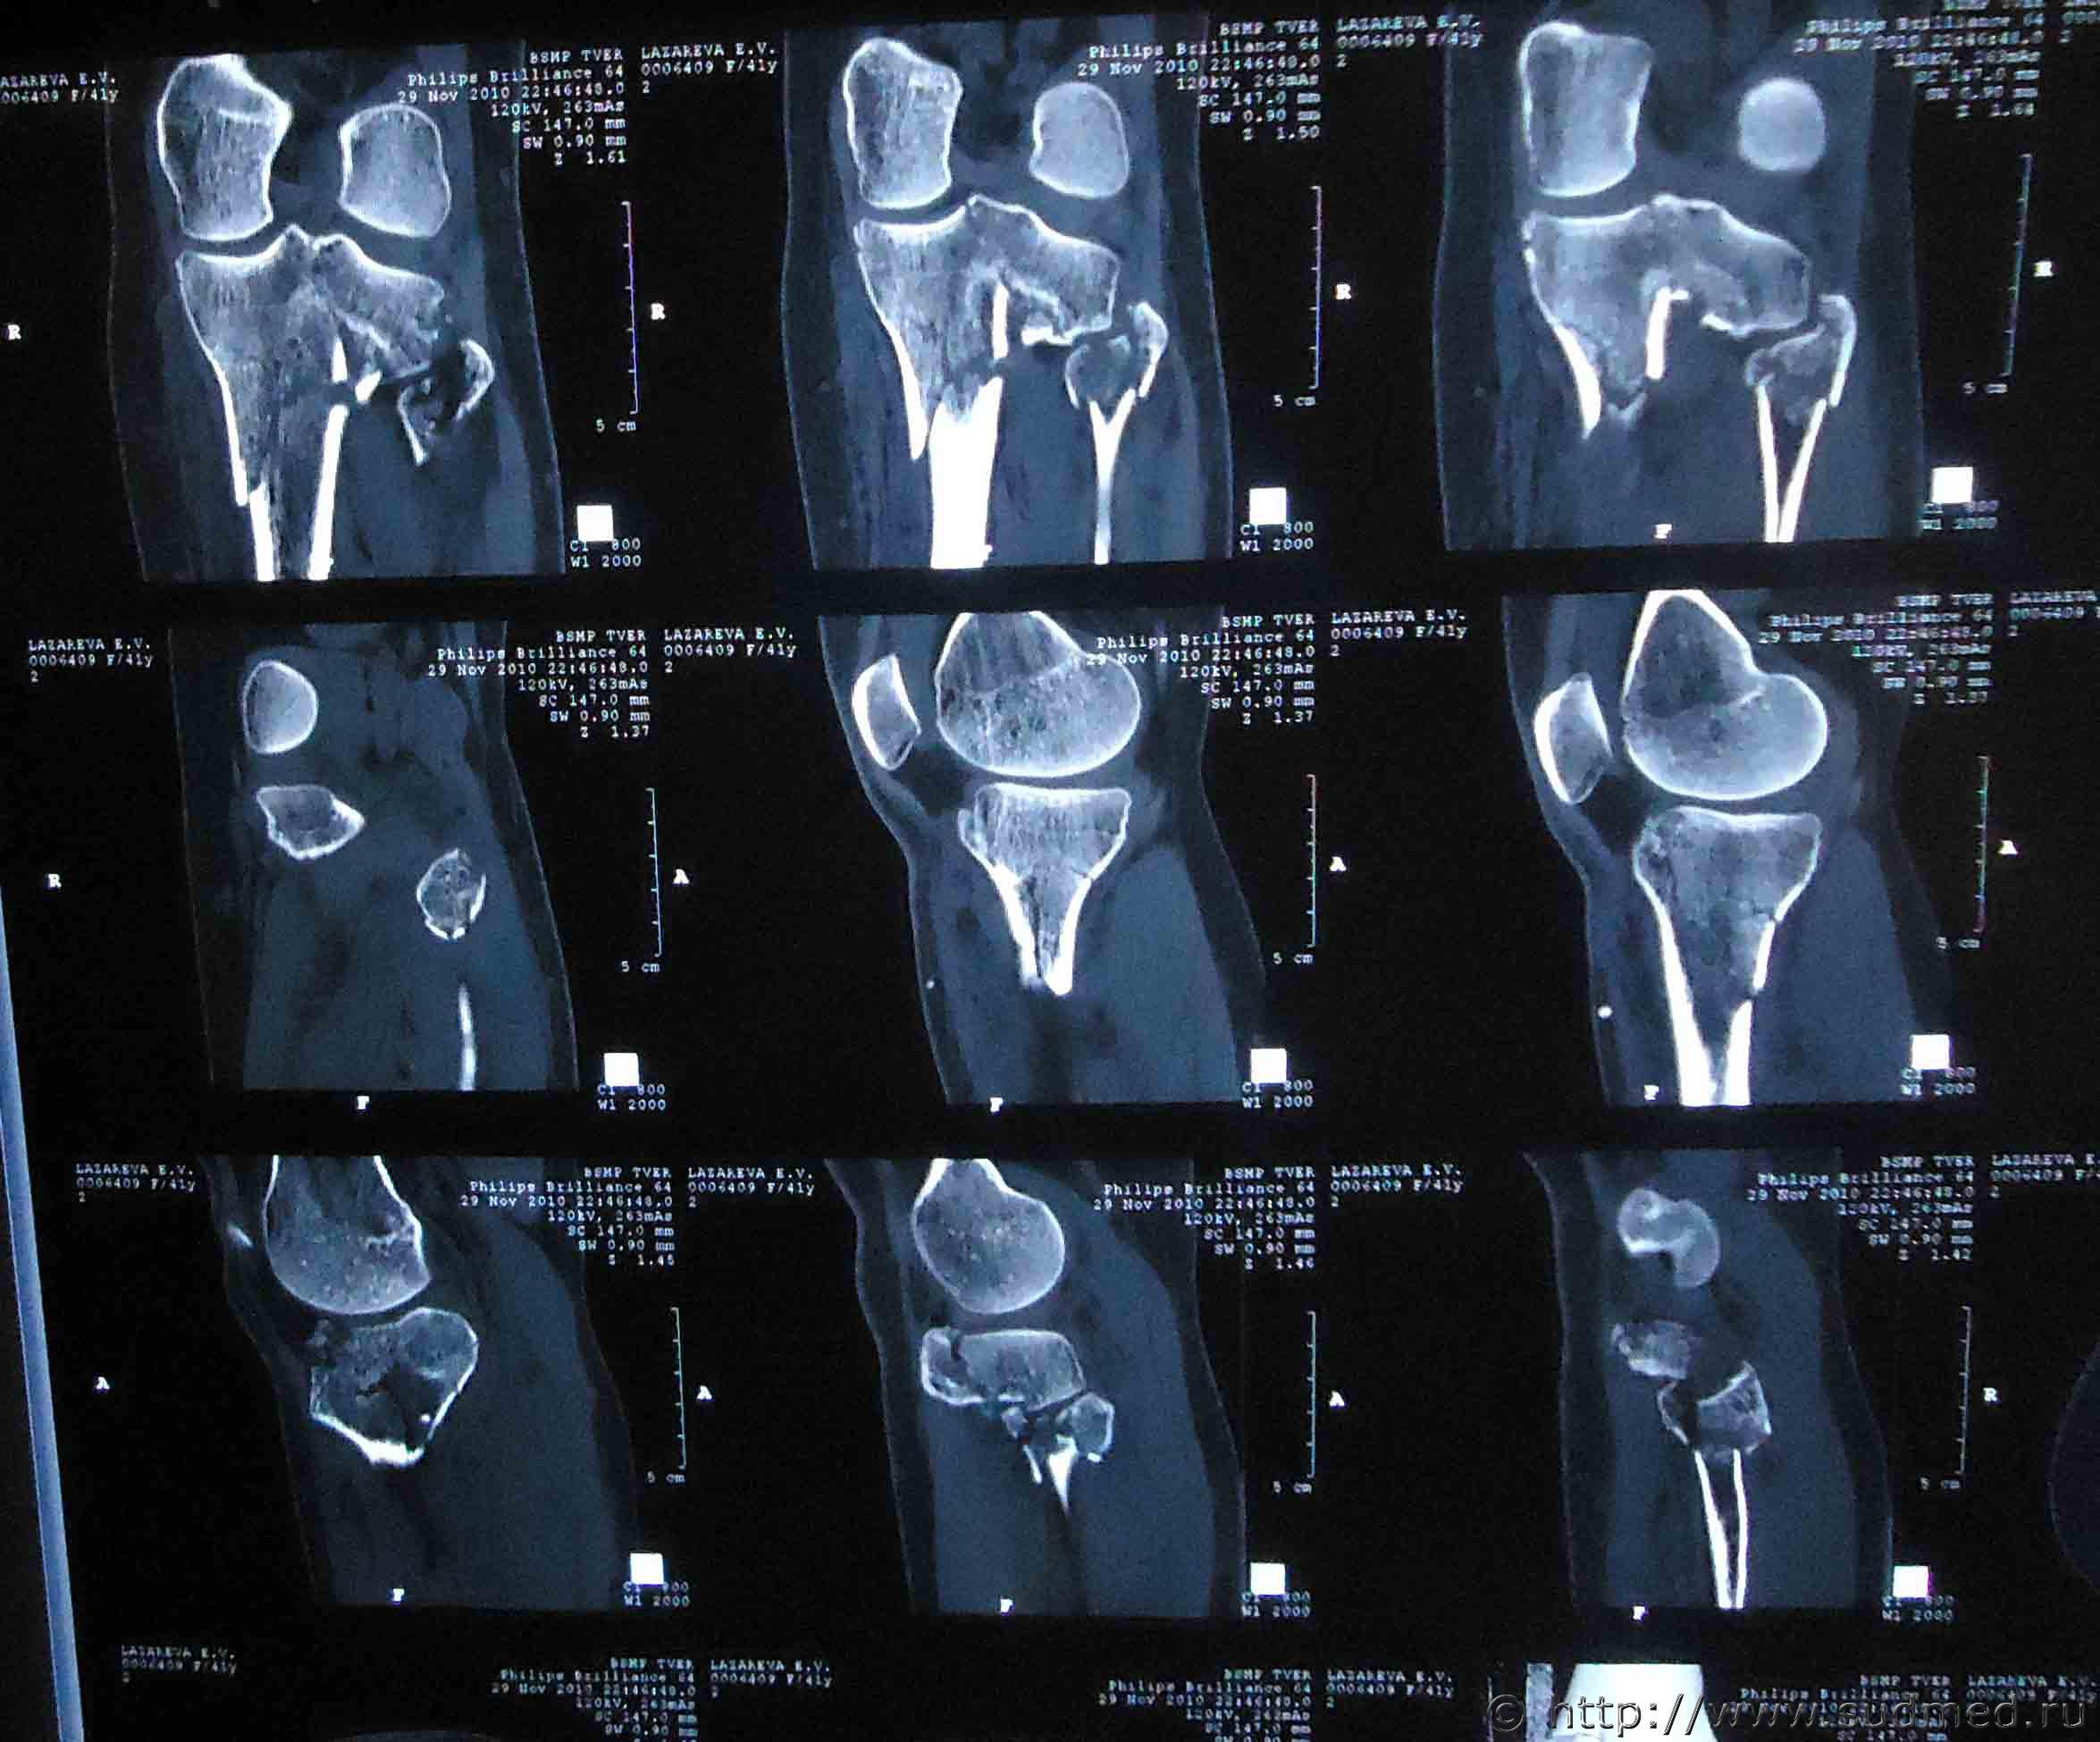

Здравствуйте. На мою жену 2 года назад был совершен наезд, при этом она получила травмы: ЗЧМТ, сотрясение головного мозга, закрытый оскольчатый внутрисуставной перелом проксимального метаэпифиза левой большеберцовой кости со смещением, закрытый оскольчатый перелом проксимального эпифиза левой малоберцовой кости без смещения, закрытый косой перелом правой ключицы средней трети со смещением отломков.

Помогите установить степень тяжести вреда и что делать для обжалования медицинской экспертизы? Снимки прилагаю